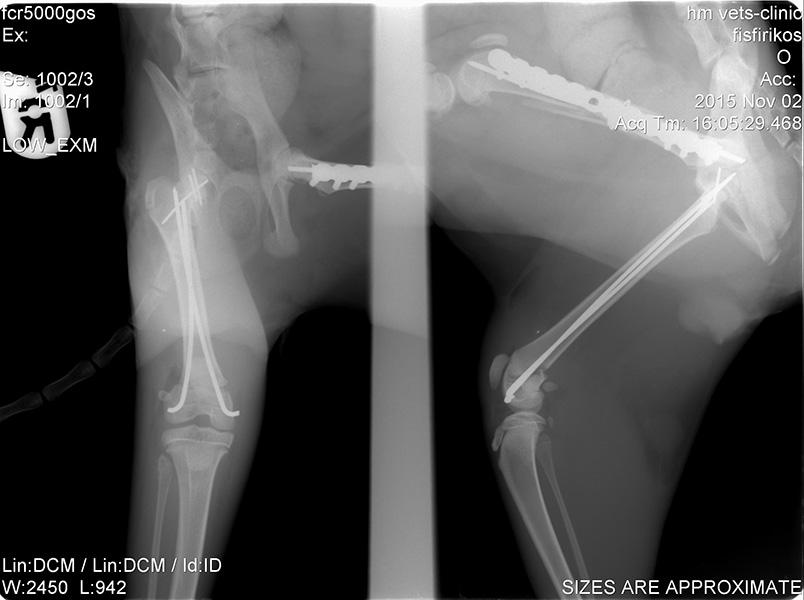

Ορθοπεδική

Ορθοπεδική

Το κτηνιατρείο hm vets αναλαμβάνει ψηφιακή ακτινογραφία, έλεγχο δυσπλασίας ισχίου, ορθοπεδική-νευροχειρουργική, χειρουργική μαλακών μορίων, οφθαλμολογία, εσωτερική παθολογία και εργαστηριακές εξετάσεις (αίματος, βιοχημικές, ανοσολογικές, ορμονολογικες, μοριακές και ιστοπαθολογικές).

Το κτηνιατρείο hm vets αναλαμβάνει ψηφιακή ακτινογραφία, έλεγχο δυσπλασίας ισχίου, ορθοπεδική-νευροχειρουργική, χειρουργική μαλακών μορίων, οφθαλμολογία, εσωτερική παθολογία και εργαστηριακές εξετάσεις (αίματος, βιοχημικές, ανοσολογικές, ορμονολογικες, μοριακές και ιστοπαθολογικές).